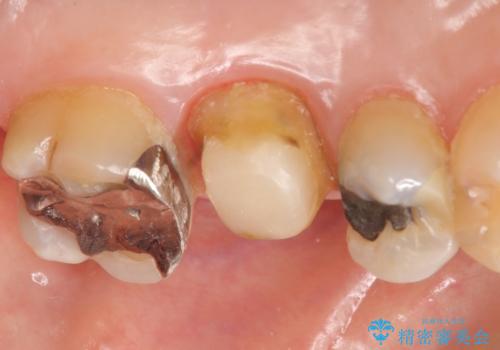

左上のできものは左上6の根尖病変が原因のフィステル(膿の出口)であったため、再根管治療を行いました。

フィステルの消失を確認後、オールセラミッククラウンによる補綴を行いました。

今回用いたオールセラミッククラウンはジルコニアフレームという白い素材の上にセラミックを盛っているため、審美性が非常に高いのが特徴です。

また、ジルコニアは人工ダイヤモンドの材料にも使われているほど高い強度を持っており、そのためオールセラミッククラウンは審美性だけでなく、奥歯やブリッジの補綴も可能とするクラウンです。